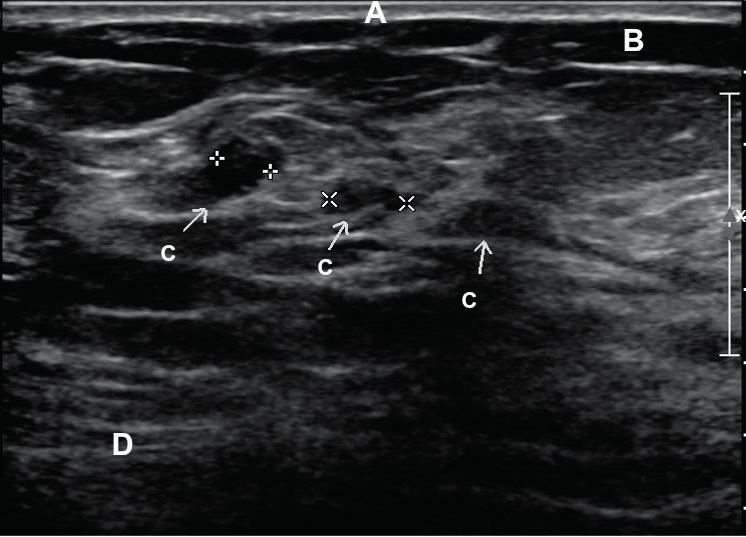

[유방의 초음파 소견]

(A) skin, (B) subcutaneous fat, (C) terminal duct lobular unit, (D) muscle